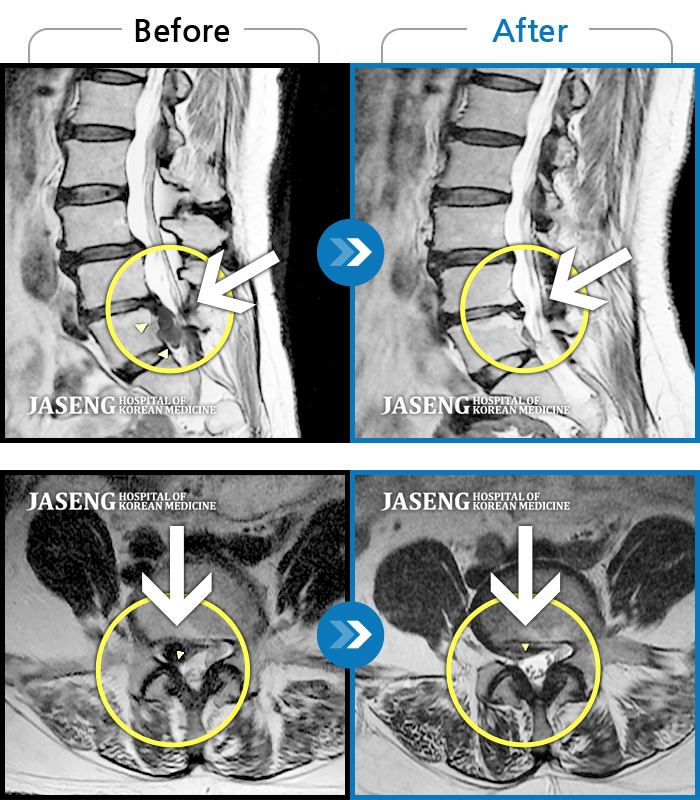

허리디스크

해운대 · 이상건 원장

허리디스크로 인한 요통

촬영시기

2018.04.21 ~ 2018.11.10

2019.01.04

조회수 244